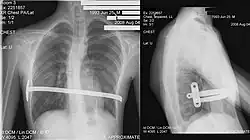

The minimally invasive repair of pectus excavatum, known as the Nuss procedure, has become a widely adopted surgical technique. This approach involves inserting a custom-bent bar into the chest to correct the sternal depression, aiming to restore a normal chest wall contour. Prior to the Nuss procedure, patients undergo thorough pre-operative evaluations, including physical examinations, imaging studies (such as CT scans to calculate the Haller index and assess cardiac compression), and cardiopulmonary function tests to determine the severity of the pectus and its impact on the heart and lungs. Studies have consistently shown positive outcomes with the Nuss procedure. For instance, an early experience with 68 patients reported that 93% achieved excellent, very good, or good results following the surgery. This procedure is also characterized by relatively short operative times (averaging around 70 minutes) and a brief hospital stay (mean of 5.7 days). While minor early complications like residual pneumothorax can occur, these often resolve spontaneously.[53]

His two-stage procedure, widely known as the Nuss procedure, involves slipping in one or more concave steel bars into the chest, underneath the sternum.[63]

The bar is flipped to a convex position so as to push outward on the sternum, correcting the deformity. The bar usually stays in the body for about two years.[53][64] When the bones have solidified into place, the bar is removed through outpatient surgery.

Although initially designed to be performed in younger children of less than 10 years of age, whose sternum and cartilage is more flexible, there are successful series of Nuss treatment in patients well into their adult life.[63][64][65]